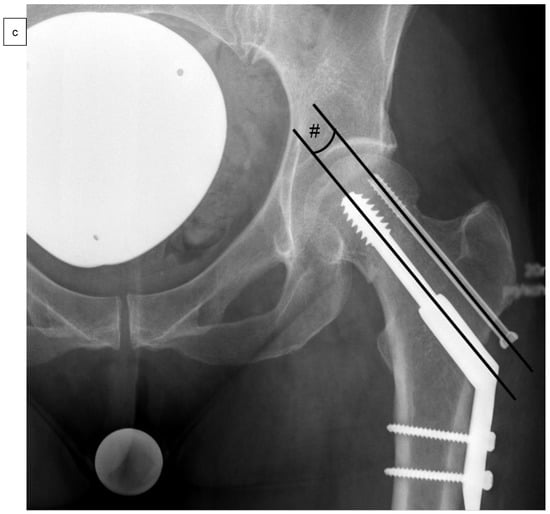

As well as epidemiological patient parameters and the Kellgren–Lawrence score at the time of hospital admission, the femoral neck angles (°) were captured in comparison to the opposite side (Figure 2a) after reduction and surgical stabilization six weeks postoperatively by using biplanar conventional radiographs. Valgus reduction was defined as a femoral neck angle of more than 5° in comparison to the opposite side. Then, the cohort group was divided into group “A”, which included patients with anatomical reduction, and group “B”, which consisted of patients with valgus reduction of the Garden type III femoral neck fracture. Further on, the angle of the 2- or 4-hole SHS plate (°), the tip-apex distance (mm) as described by Baumgaertner et al. (Figure 2b), and the angle between SHS and ARS (°) were measured in frontal (Figure 2c) and axial planes (Figure 2d) of the intraoperative or postoperative X-rays [].

Figure 2.

Measurement of the femoral neck angle (*) compared to the contralateral side (°), defined as the angle between the femoral neck axis and the bisecting line of the femoral shaft (a). The tip-apex distance (TAD) was defined as the calibrated summation of the distance between the tip of the SHS and the apex of the femoral head on anteroposterior and (not demonstrated) lateral radiographs (mm) (b), and the angle between SHS and ASR in the frontal plane (#) (c) and the axial plane (x) (d) by using biplanar conventional radiographs, six weeks postoperatively.